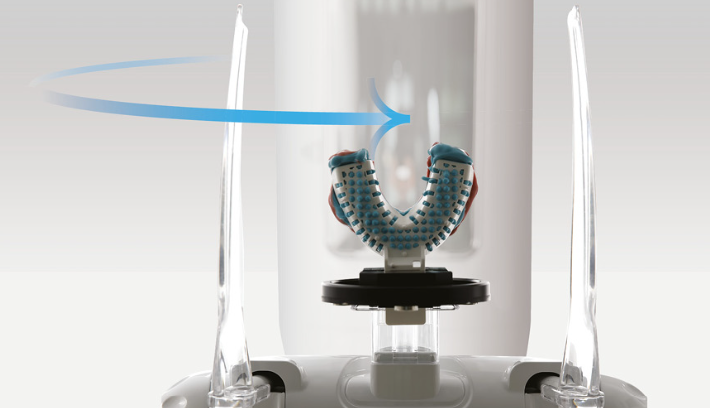

Escaneo cómodo y sencillo

ODONTOLOGÍA IMPULSADA POR EL ROSTRO

Escáner Facial 3D + CBCT + Escáner Intraoral

Libere el potencial de las SOLUCIONES BASADAS EN EL ROSTRO: obtenga resultados de tratamientos personalizados y estéticamente agradables, al capturar el espectro completo de la anatomía facial y dental. La avanzada tecnología de RAYSCAN S garantiza imágenes completas de los huesos faciales y dentales, todo mientras minimiza la exposición a la

radiación. Con nuestros escáneres facial e intraoral 3D, la planificación específica para cada paciente se vuelve una herramienta transformadora e indispensable, preparada para mejorar e inspirar vidas.

Un escaneo con todos los detalles

RAYSCAN S puede capturar una región completa de la anatomía con facilidad y precisión. Su extraordinaria capacidad para capturar toda la anatomía en un sólo escaneo es realmente impresionante.

Escaneo de impresiones

RAYSCAN α 3D utiliza avanzada tecnología de escaneo 3D para capturar datos de impresiones físicas y modelos de yeso, que posteriormente se utilizan para generar el archivo STL requerido por aplicaciones CAD/CAM.